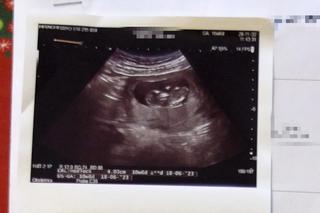

Sikorowie mają już dwójkę dzieci w wieku 8 i 11 lat, są szczęśliwą, kochającą się rodziną. Kiedy w połowie października test ciążowy pokazał, że pani Paulina jest w ciąży, nie posiadali się z radości. Od razu umówiła się na wizytę w prywatnym gabinecie doktor K. , doświadczonej ginekolożki z wieloletnią praktyką. - Ósmy tydzień ciąży, jednak to poronienie chybione, płód jest martwy - diagnoza, którą lekarka postawiła po przeprowadzeniu badania USG zdruzgotała ich oboje, ponieważ już raz musieli mierzyć się z taką tragedią. Do domu wracali w milczeniu, łykając łzy. - Nie spałam całą noc, nie wierzyłam w to - wspomina pani Paulina.

Nazajutrz pojawili się w SPZOZ w Lubartowie ze skierowaniem na usunięcie płodu. Zajął się nią wtedy dr Mohammad Suleiman, który postanowił zbadać ją jeszcze raz. Pojawiła się nadzieja. - Powiedział, że nie widzi żadnej ośmiotygodniowej ciąży, tylko maksymalnie trzytygodniową, co zgadzałoby się z moimi spostrzeżeniami - opowiada kobieta. - Zlecił dodatkowe badania, przestrzegając nas, żebyśmy nie nastawiali się na żadne z rozwiązań. I choć wyniki badań zdawały to potwierdzać, na drugi dzień dwoje innych lekarzy jeszcze raz zbadało pacjentkę, potwierdzając przy okazji rewelacje dr K. - ciąża jest martwa, należy ją usunąć.